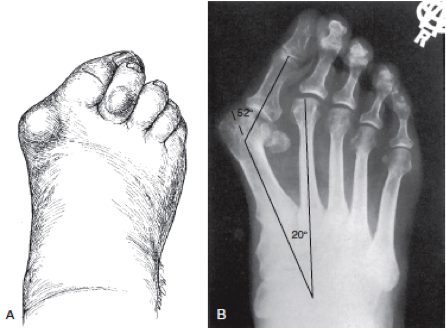

Es por esto que es común la formación de callosidades o ampollas en el dorso de los dedos (Fig. 4), la presencia de dolor o rigidez en la planta del pie, calambres, diferentes tipos de lesiones en las uñas e incluso al largo plazo se puede provocar la desviación del primer ortejo del pie (dedo gordo), lo que se conoce como hallux valgus o “juanete” (Fig. 5). Además, en casos extremos, debido a la gran compresión que puede generar el calzado en caso de ser muy pequeños, podría generar daño a nivel de los nervios del pie, generando adormecimiento, dolor y debilidad.

Figura 5. Hallux valgus, conocido también como “juanete”.